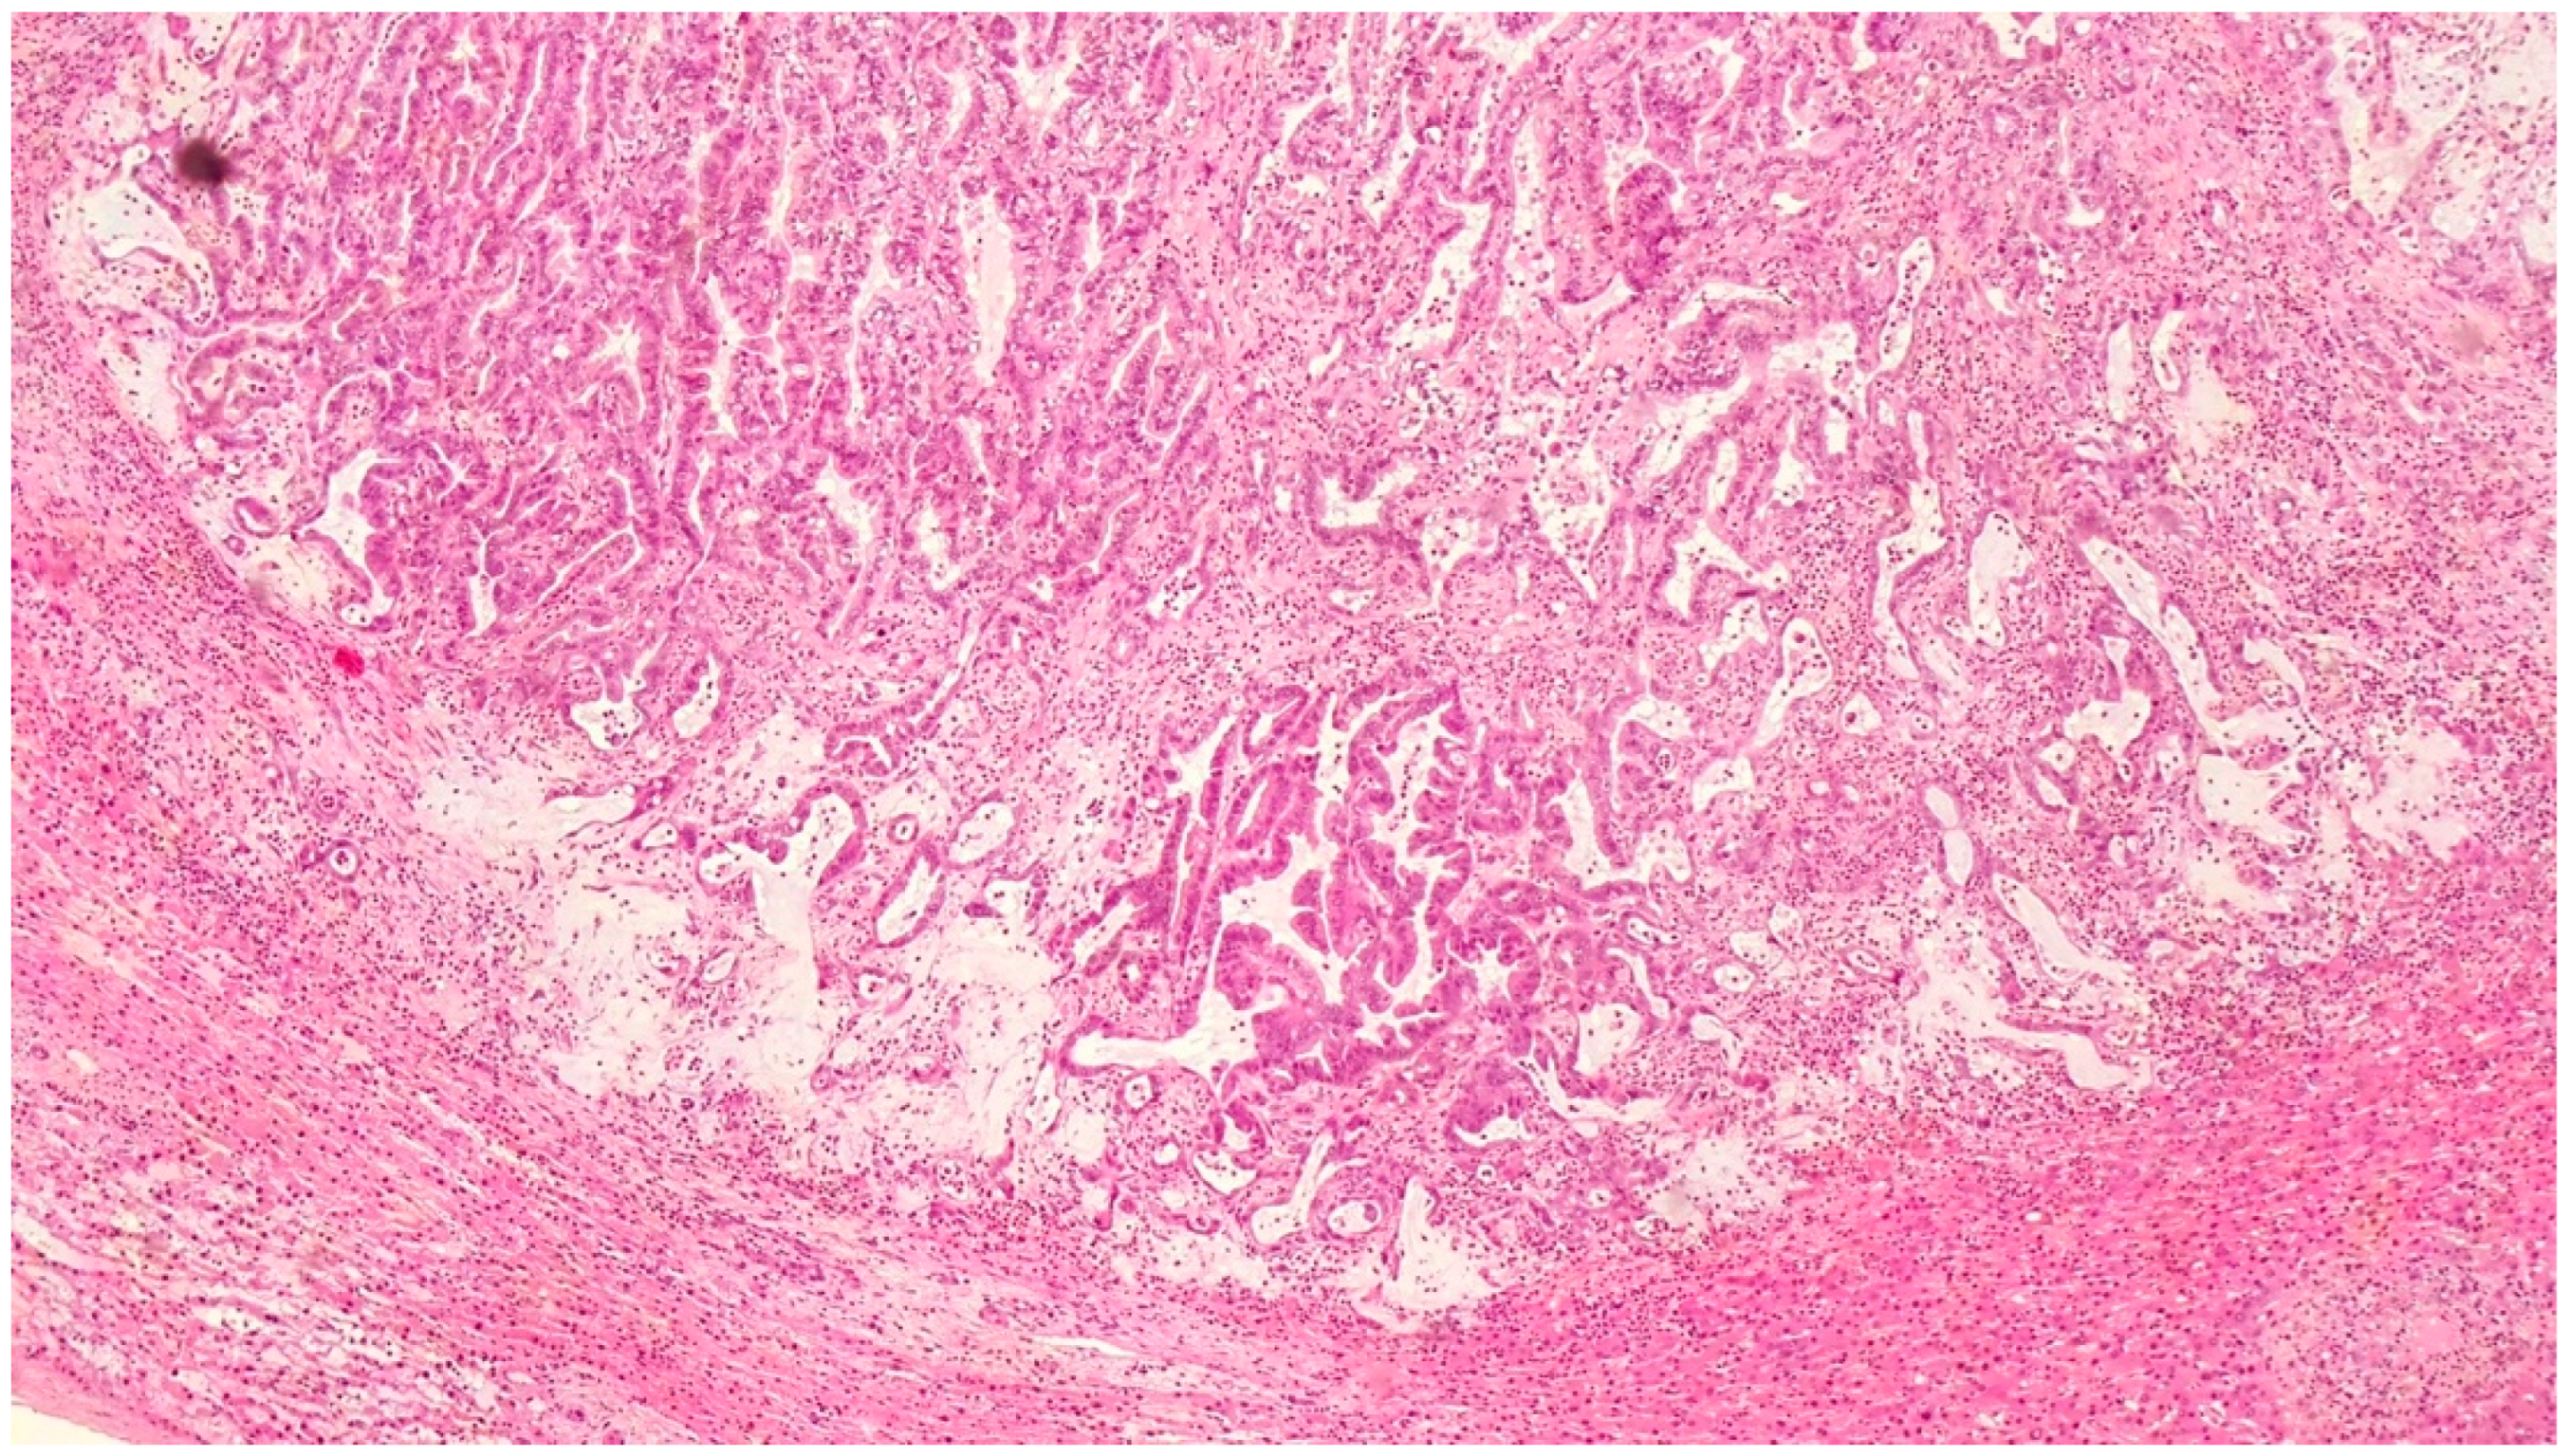

2. Case Report 1

| Histopathological Findings | IPNB with foci of adenocarcinoma, oncocytic appearance, varying degrees of dysplasia, mucus within cyst | Adenocarcinoma with papillary clear cell and mucinous appearance, gland ectasis, cystic or pseudocystic aspects |